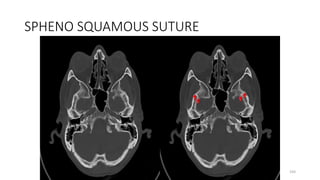

SPHENO SQUAMOUS SUTURE

177